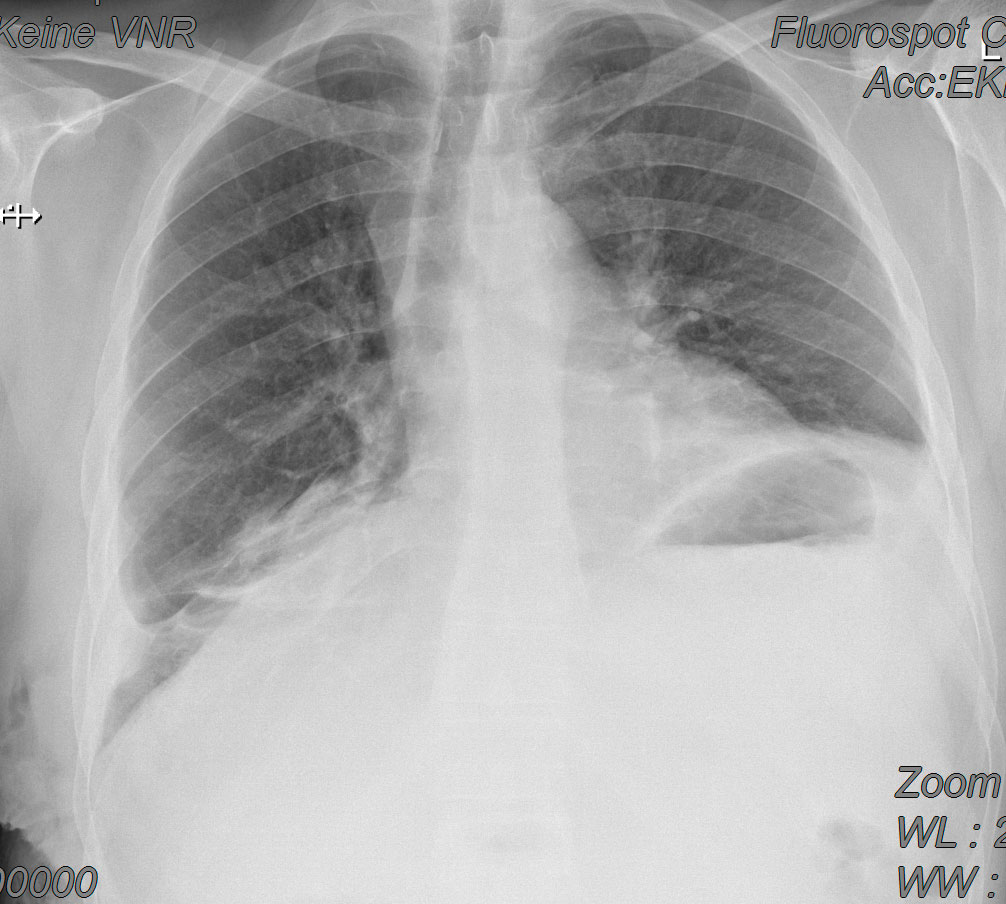

Lungenkrebs

Lungenkrebs befällt etwa 25 Prozent aller Krebskranken und gilt als häufigster Tumor beim Mann. Doch auch immer mehr Frauen sind betroffen. Die chirurgische Therapie ist für uns Mittel der Wahl, sofern keine Fernmetastasen vorhanden sind. Dabei können wir in unserer Klinik technisch hoch anspruchsvolle Lungenoperationen auf endoskopische Weise videoassistiert vorgenommen werden.

- Lungenrundherd (Lungenverschattung)

Chronisch-obstruktive Bronchitis (COPD) und Lungenemphysem

Das Lungenemphysem führt zu einer krankhaften Überblähung der Lunge. Die Behandlung besteht aus Raucherentwöhnung, bronchienerweiternden Medikamenten, Sauerstoffgabe. Im fortgeschrittenen Stadium kann in ausgewählten Fällen durch eine lungenverkleinernde Operation (LVRS) eine Verbesserung der Symptomatik erreicht werden.

Lungenkollaps (Pneumothorax)

Unter einem Lungenkollaps/Pneumothorax (pneu = Luft, Thorax = Brustkorb) versteht man ein Eindringen von Luft in den Lungenfellraum (Pleuraraum). Die Luft kann von innen oder von außen durch eine Verletzung der Brustwand in den Pleuraraum gelangen. Die Folge davon ist, dass sich die Lunge nicht mehr ausdehnen kann und in sich zusammenfällt. Ursachen hierfür kann ein Rippenbruch, aber auch das Platzen von aufgetriebenem Lungengewebe (Lungenemphysem) sein.